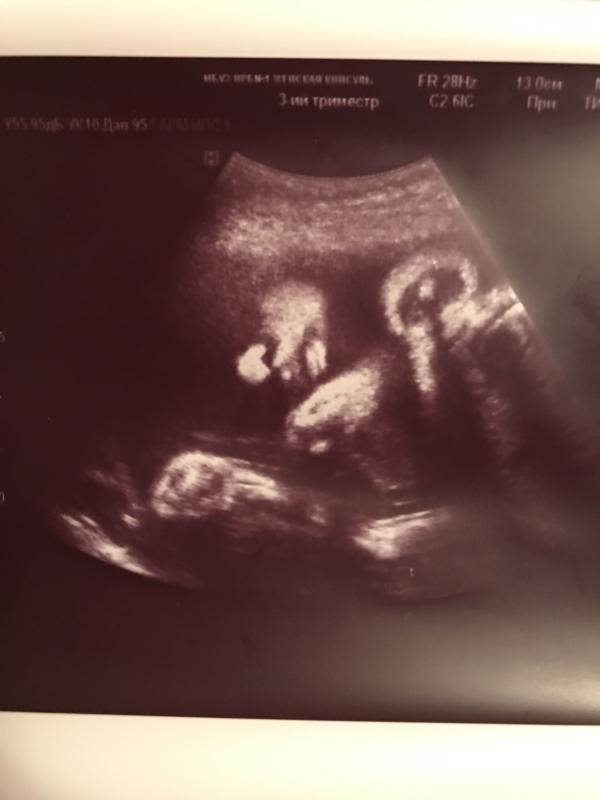

Мужу,папе,маме пришлось долго объяснять что здесь что) Я сразу увидела любимые щечку,носик и губки☺

Да сразу ведь видно))) после того как мы на 3д узи пытались что-то разглядеть, я могу все

@kitari.work, сложно с первого раза разобраться, ищешь плод, а там только голова помещается 😂😂😂

Оооо... 10 минут я смотрела и не могла понять, даже после объяснения, думаю ну все горе мать и так сказывается беременность что ничего не понимаю, а нет фото повернула и увидела,вы прекрасны))))))))

@superolya, моя мама там вообще пыталась найти целого человечка,пока не объяснила, что тут только лицо)

@superolya, у меня наверное даёт знать о себе год работы в кабинете УЗИ) сразу все вижу)